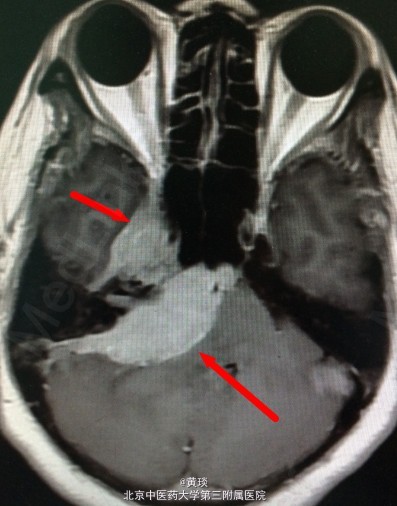

患者47岁,无明显诱因出现头痛1年,无恶心呕吐,无头晕,无呼吸心跳改变,与当地中医院中草药治疗,疗效差,近半月明显加重,遂于我院就诊。

头颅MRI提示:桥小脑角区巨大脑膜瘤

诊断:脑膜瘤 处理:开颅切除